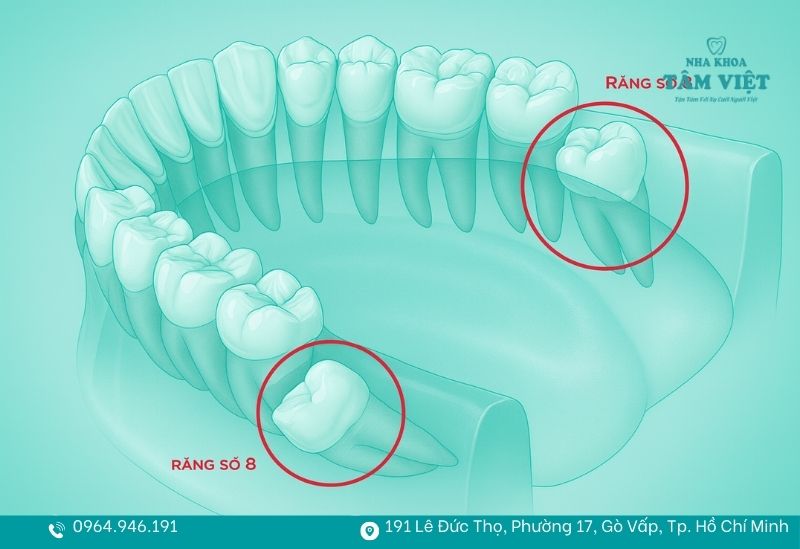

Răng số 8, thường được gọi là răng khôn, là chiếc răng mọc cuối cùng trên cung hàm. Ở vị trí hàm dưới, răng số 8 nằm ngay phía sau răng số 7 và thường bắt đầu xuất hiện trong độ tuổi từ 17-25.

Do mọc sau cùng nên răng số 8 hàm dưới thường không còn đủ khoảng trống để phát triển bình thường. Hệ quả là chiếc răng này dễ bị mọc lệch, mọc ngầm hoặc chỉ nhú một phần trên nướu, gây ra nhiều vấn đề như đau nhức, viêm lợi, chèn ép răng kế cận và ảnh hưởng đến cấu trúc toàn hàm.